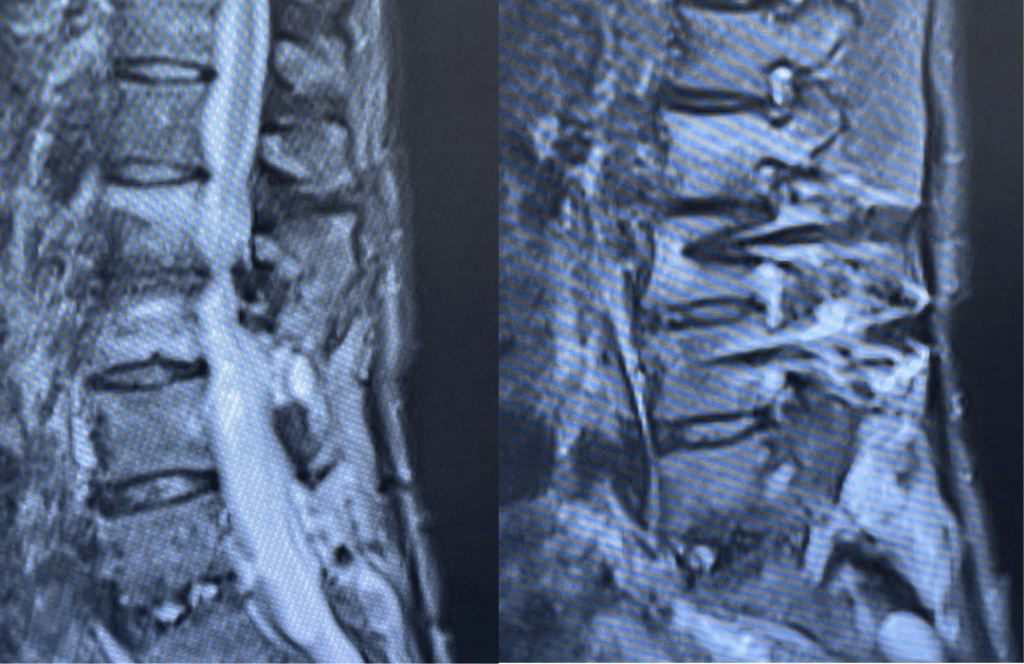

Spine:

Cervical Laminectomy and Fusion

Author: William Sonstein M.D., F.A.C.S., Read More!